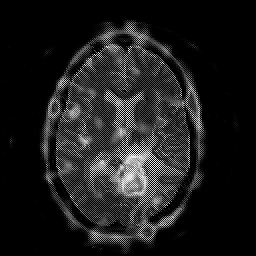

Glioblastoma multiforme overlay -- Slice #30

[Home][Help][Clinical][Tour 1][Tour 2][Tour 3] Slice 30